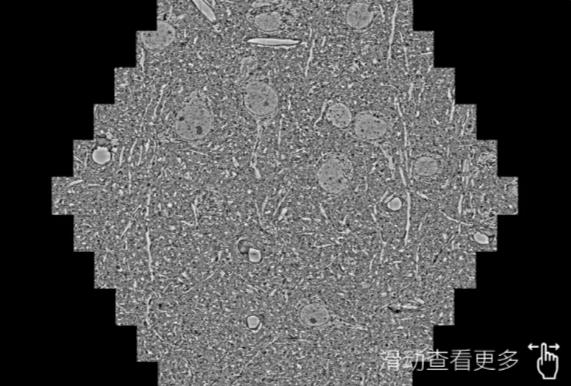

鼠脑切片。左图使用鹰潭蔡司鹰潭扫描电镜MultiSEM706对165μmx143pm面积区域成像,耗时仅需1.5秒。右图为鼠脑切片中30μm区域放大效果。样品由芝加哥大学B.Kasthuri提供。

使用蔡司高速鹰潭扫描电镜MultiSEM对1mm²人脑皮层组织进行高分辨成像,并对其中的各种细胞结构进行三维重构分析。左图展示了2x3mm²组织平面中锥体神经元的三维重构效果。右图显示了局部体积神经元三维重构。图像由哈佛大学chtman实验室提供,渲染图由D. Berger 制作。